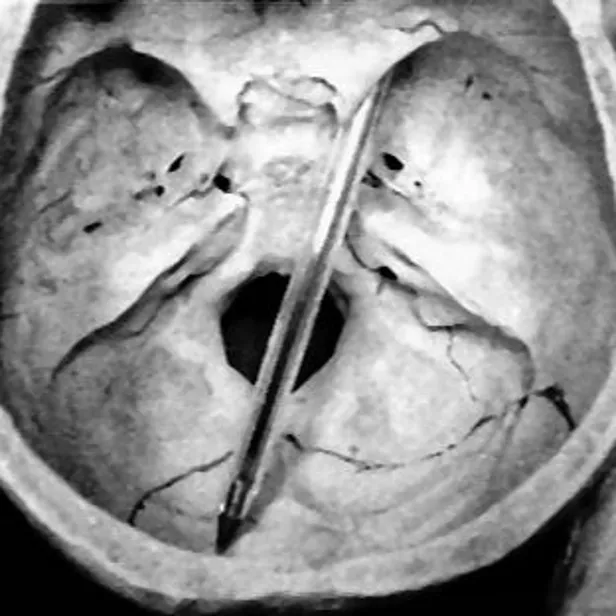

Nadat de patholoog-anatoom de schedel van het slachtoffer heeft gelicht – hij verkeert dan nog in de veronderstelling dat Mary een hersenbloeding heeft gehad – treft hij tot zijn grote verbazing in de hersenen een intacte balpen aan. De pen, een zwarte van het merk Bic, is via het rechteroog schuin het hoofd binnengedrongen en linksonder geëindigd. De sectiearts stelt vast dat het slachtoffer binnen één à twee seconden in coma moet zijn geraakt en daarna niet langer dan een kwartier tot dertig minuten kan hebben geleefd. In zijn verslag gebruikt de patholoog-anatoom het woordje ‘steekwond’ en dat is voor de recherche het startsein voor een omvangrijk onderzoek. Blijkbaar is er opzet in het spel en heeft zich daar aan de Witte Rozenstraat dus een misdrijf afgespeeld. Dat er ook aanwijzingen zijn dat Mary, die Birkenstock-sandalen droeg, met een pen in de hand over een losliggend kleedje kan zijn gevallen, daar heeft opeens niemand het meer over.